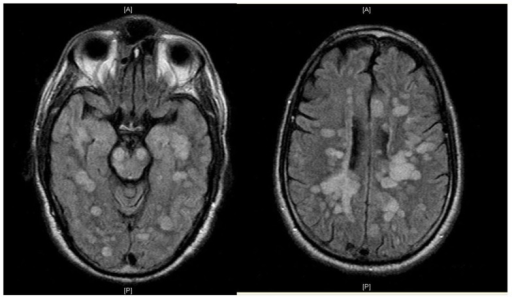

CADASIL/CARASIL

cerebral autosomal dominant/recessive arteriopathy with subcortical infarcts and leukoencephalopathy

NOTCH3 mutations

causes progressive cognitive decline, recurrent ischemic strokes (often lacunar), migraines

MRI features symmetric WM hyperintensities, including in anterior temporal poles